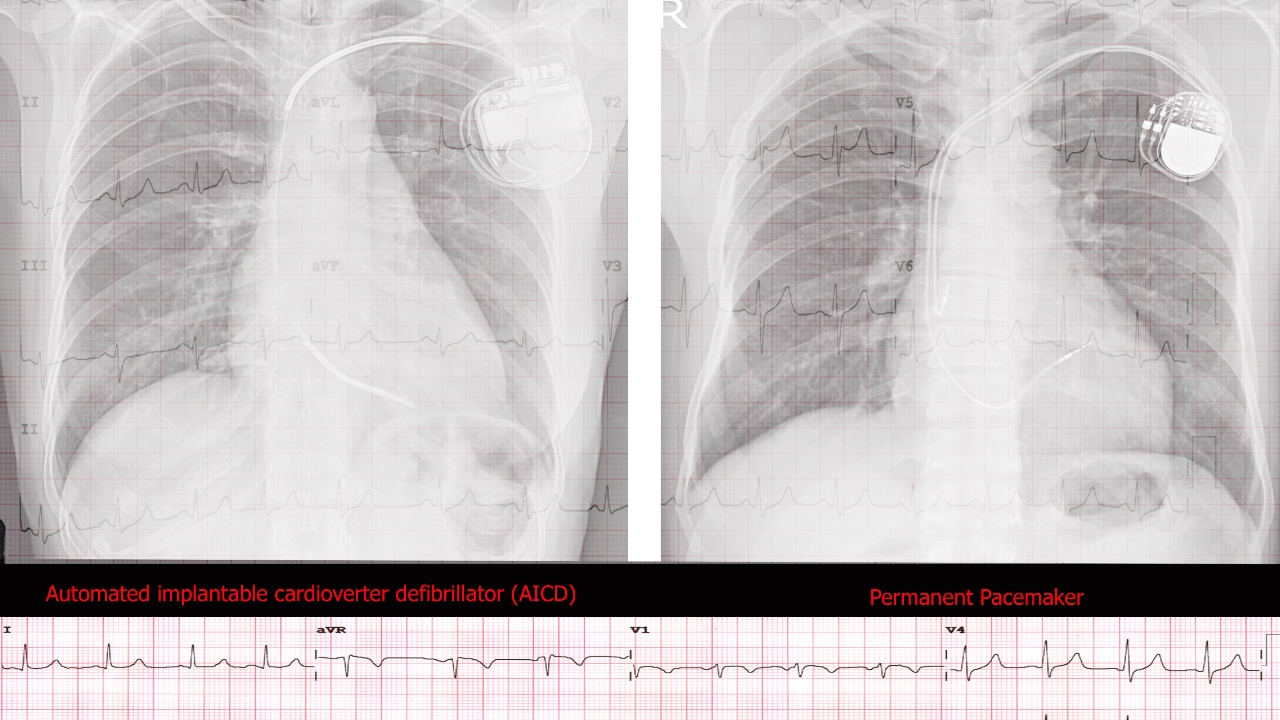

วันที่ 6 สิงหาคม 2568 สำนักข่าวต่างประเทศรายงานว่า รัฐเทนเนสซีของสหรัฐฯ ดำเนินการประหารชีวิตนายไบรอน แบล็ก นักโทษชายวัย 69 ปี ด้วยการฉีดยาพิษเข้าร่างกาย โดยไม่ได้ปิดการทำงานของเครื่องกระตุ้นหัวใจชนิดฝังในร่างกาย (Implantable Cardioverter Defibrillator: ICD) ท่ามกลางความกังวลว่าอุปกรณ์กระตุ้นหัวใจอาจช็อกหัวใจให้กลับมาทำงานอีก หลังยาพิษออกฤทธิ์ ซึ่งทำให้เกิดภาวะตายแล้วฟื้นวนลูป เจ็บปวดทรมานเกินความจำเป็น

รายงานข่าวระบุว่า นักโทษรายนี้มีอาการป่วยเรื้อรังหลายโรค รวมถึงภาวะสมองเสื่อม ไตวาย หัวใจล้มเหลว ต้องนั่งรถเข็น และใส่เครื่องกระตุ้นการทำงานของหัวใจแบบฝังในร่างกาย โดยทีมทนายความได้ยื่นเรื่องขอให้ศาลสั่งปิด ICD ก่อนการประหาร เนื่องจากอาจกระตุ้นหัวใจโดยไม่จำเป็น แต่คำสั่งดังกล่าวถูกศาลฎีกาของรัฐเทนเนสซีเพิกถอนเมื่อปลายเดือนกรกฎาคมที่ผ่านมา โดยให้เหตุผลว่า "ศาลชั้นต้นไม่มีอำนาจออกคำสั่ง"